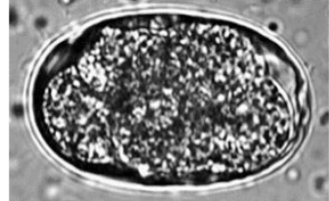

Toxocara canis. (Canine Roundworm)

Other info

Found in intestinal track

Pitted outer shell

Dark pigmented centre